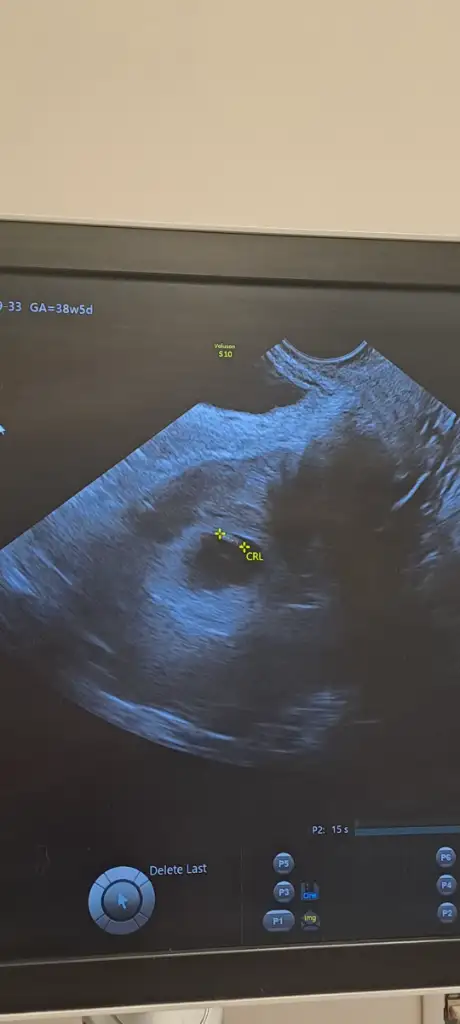

Bunada bakar mısınız rica edersemkız gibi

Bunada bakar mısınız

çok küçük ama kese kız gibiBana da yorum yapar mısınız 8 haftalık vajinal bakıldı

Ayy insallah ağzınız bal yesinçok küçük ama kese kız gibi